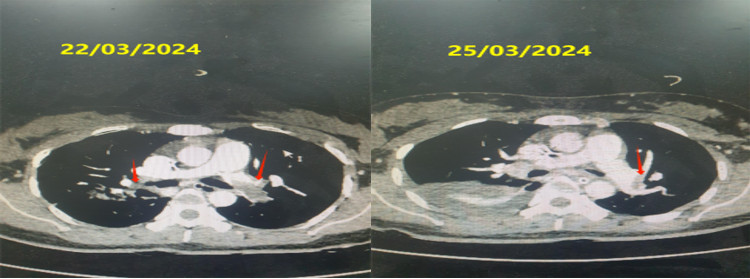

Bệnh nhân được chụp cắt lớp vi tính dựng hình động mạch phổi cấp cứu. Kết quả có hình ảnh huyết khối thân chung động mạch phổi trái và huyết khối gần hoàn toàn nhánh thùy dưới 2 phổi.

| Hình ảnh chụp cắt lớp vi tính động mạch phổi của bệnh nhân trước và 72 giờ sau dùng tiêu sợi huyết. (Mũi tên đỏ chỉ vị trí huyết khối) - Ảnh BVCC |

Toàn trạng bệnh nhân tiến triển khá hơn từng ngày, ý thức bình phục nhưng tiếp xúc còn chậm chạp, huyết động ổn định và cắt thuốc co mạch. Bệnh nhân được chụp lại phim cắt lớp vi tính động mạch phổi để kiểm tra đánh giá hiệu quả điều trị.

Sau 3 ngày vào viện (25/03/2024), hình ảnh cắt lớp vi tính động mạch phổi cho thấy chỉ còn huyết khối các nhánh phân thùy dưới phổi trái. Kết quả chụp lại phim cắt lớp vi tính động mạch phổi ngày 08/04/2024 không còn thấy huyết khối trong động mạch phổi 2 bên. Bệnh nhân ổn định ra viện sau 19 ngày điều trị.